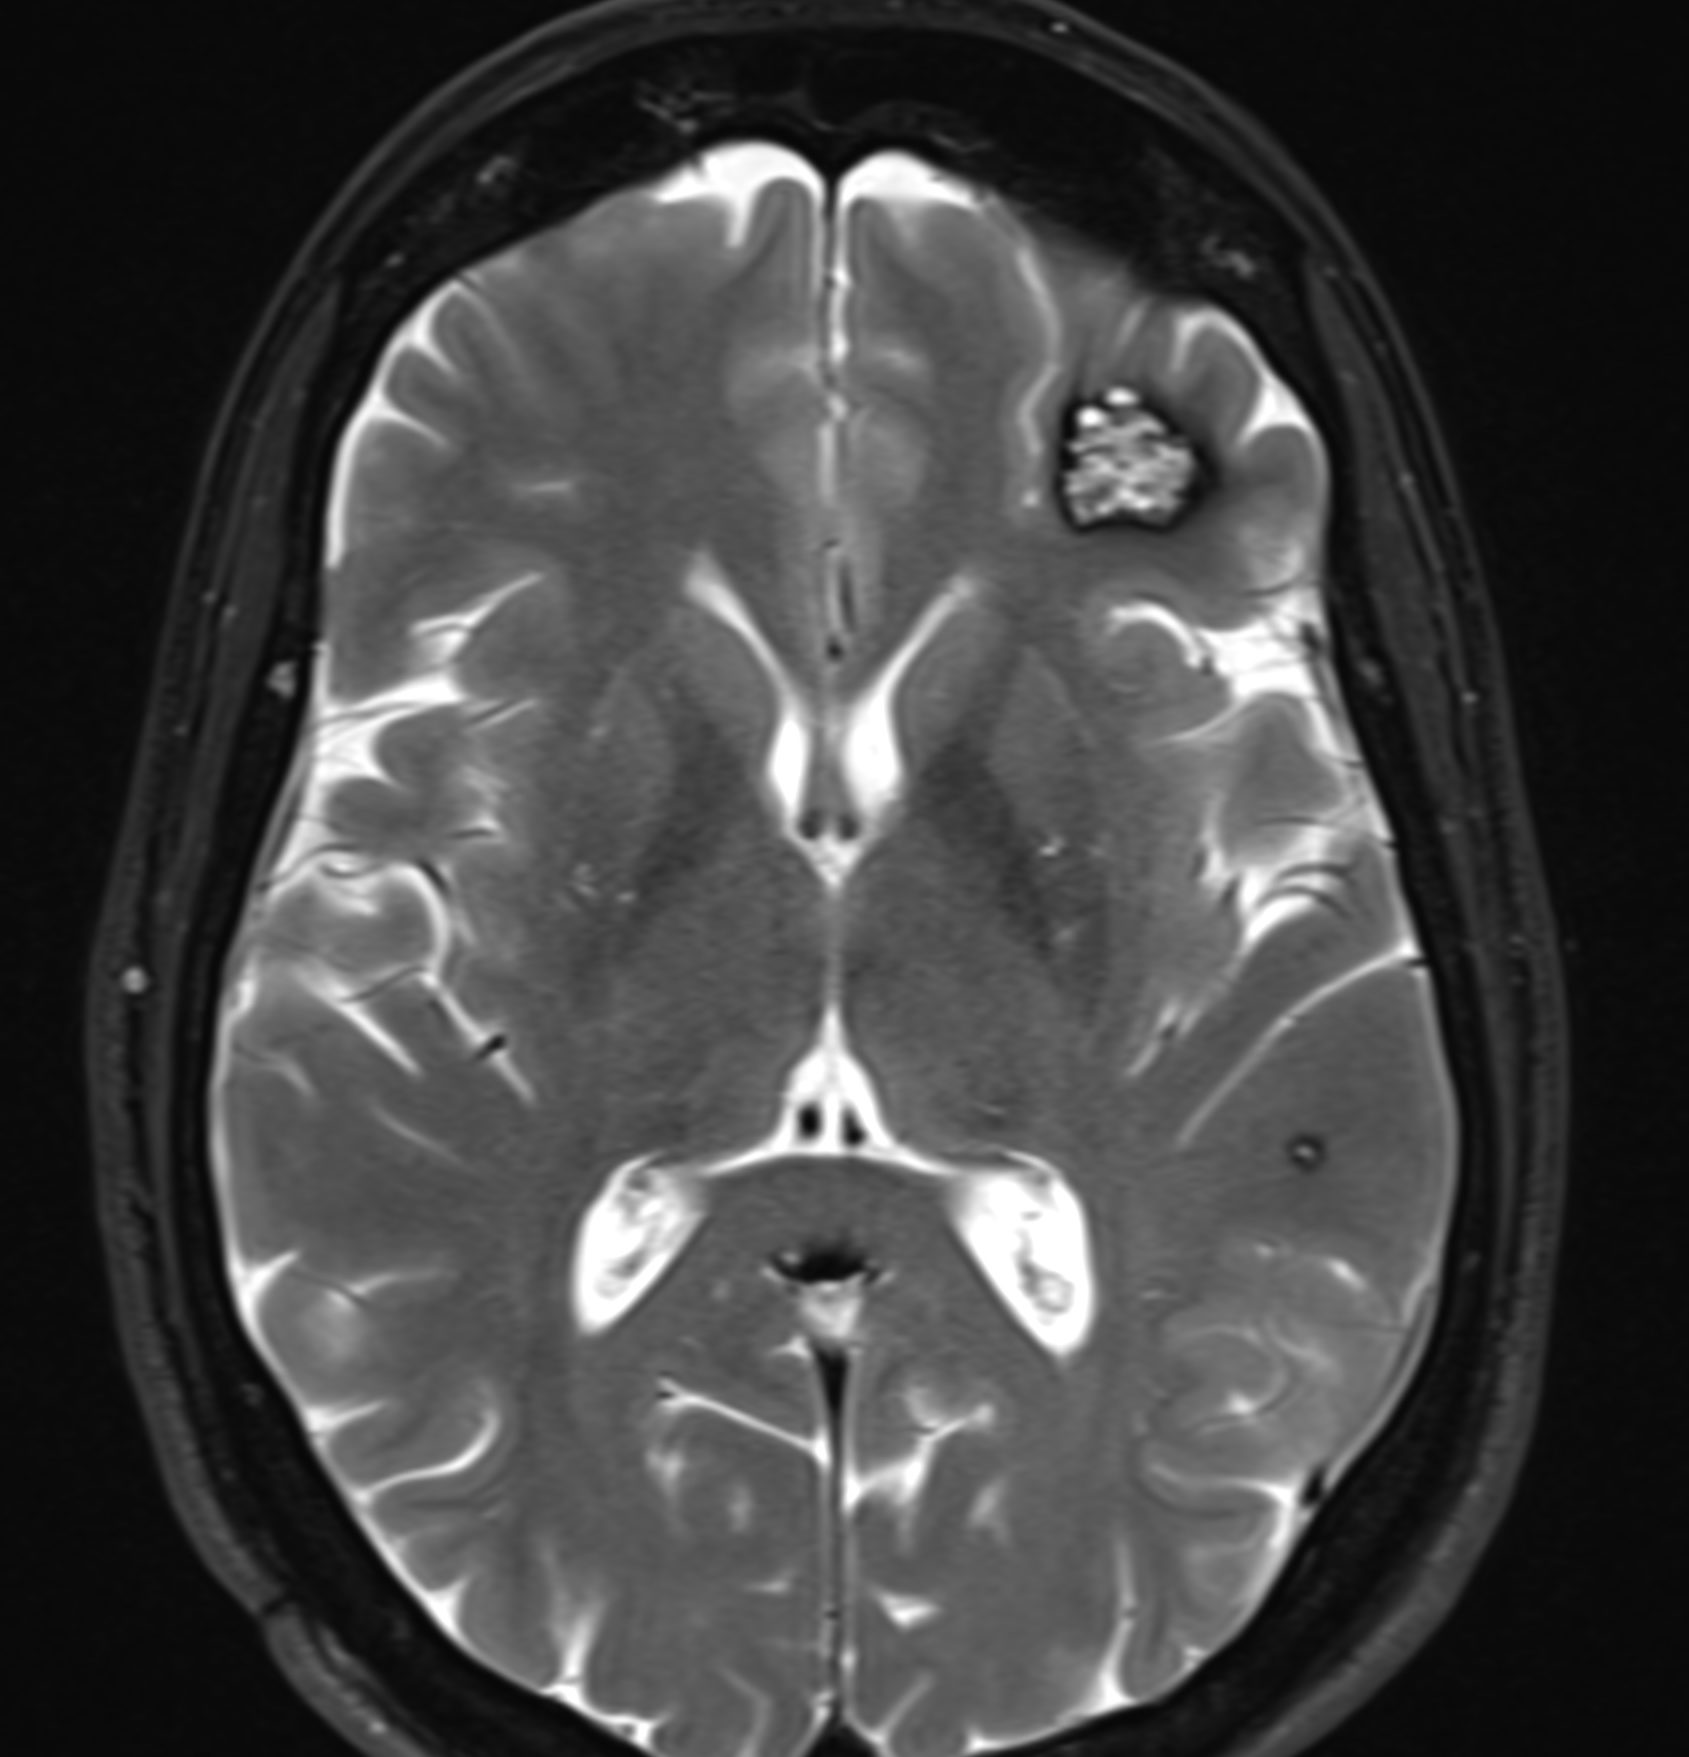

Il cavernoma cerebrale è una patologia vascolare cerebrale rappresentata da una malformazione venosa in cui le vene si agglomerano nel parenchima cerebrale invece di costituire una vena normale. Le manifestazioni neurologiche piu’ frequenti sono delle crisi epilettiche, un deficit motorio oppure una cefalea ricorrente. Il trattamento classico di questa patologia è l’asportazione chirurgica tramite craniotomia sotto anestesia totale. L’alternativa alla chirurgia può essere la radioterapia se le lesioni sono considerate non operabili.

Cavernoma cerebrale

Per fortuna, la maggior parte dei cavernomi cerebrali sono asintomatici e stabili nel tempo. In questi casi, non è necessario asportarli e si possono svolgere dei controlli radiologici regolari. Il Dr Robert e la Dr.ssa Bonasia hanno una grande esperienza nella presa decisionale e nei controlli dei cavernomi cerebrali. Realizzano gli interventi per i cavernomi cerebrali alla Clinique La Source di Losanna.